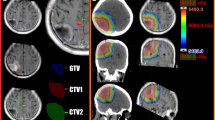

The hypo-IMRT technique was previously reported [3]. In brief, IMRT with a simultaneous integrated boost was used to deliver differential radiation doses to different targets. The gross tumor volume (GTV) was defined as any contrast-enhancing residual tumor on the post-operative T1-weighted post-contrast MRI plus the entire surgical cavity. The clinical tumor volume (CTV) was defined as the abnormality on the T2-weighted MRI. For the hypo-IMRT/TMZ alone trial, planning target volume 1 (PTV1) was defined as the GTV plus a 0.5 cm margin and planning target volume 2 (PTV2) the CTV plus a 0.5 cm margin. In the hypo-IMRT/TMZ/BEV trial, PTV1 was defined as the GTV plus a 1 cm margin and PTV2 the CTV plus a 1 cm margin. On both trials PTV1 received 60 Gy and PTV2 30 Gy simultaneously in ten fractions over 2 weeks.